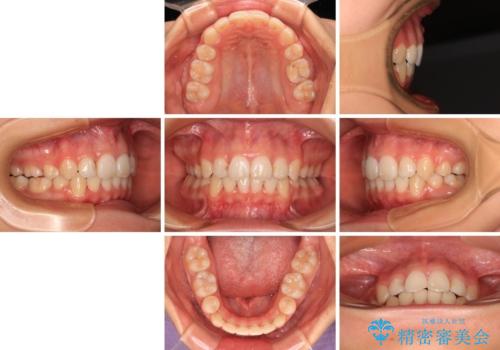

補助装置を併用したおかげでスムーズに奥歯の咬み合わせを改善することができ、我々も予想できないくらい理想的な仕上がりにすることができました。

- 咬み合わせと、前歯のデコボコや八重歯、飛び出した口元を気にして来院された患者様です。

補助装置を用いて奥歯の咬み合わせを改善しながら歯列を後方に移動させ、上下左右第一小臼歯を4本抜歯することで八重歯や口元の突出感を改善することとしました。